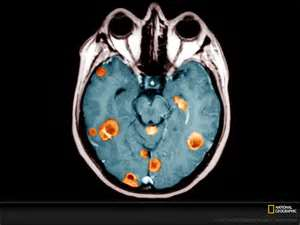

Brain